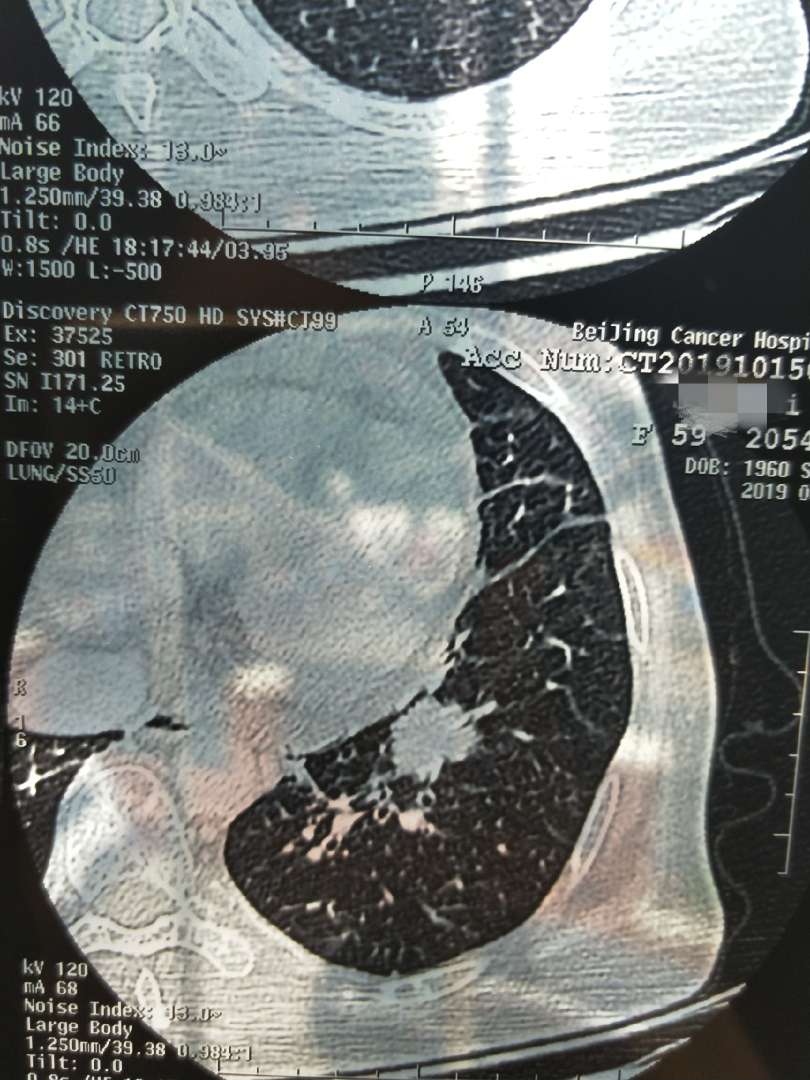

★10.6日左肺下叶结节20*14mm,纵膈多发肿大淋巴结部分融合40*21mm,心包少量积液,左肾上腺占位。

★颅脑左额叶和顶叶结节,双侧基底节区及半卵圆中心多发腔隙灶。